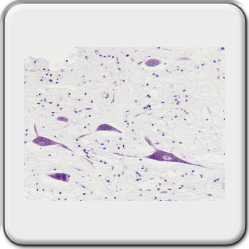

Nissle substance in motor neurons, cresyl violet acetate staining

Purpose of the slide: To visualize RER and free ribosomes in the cell body of neurons.

The large nucleus has a prominent nucleolus[2] and finely divided chromatin. Also found are many free polyribosomes and a highly developed RER (rough endoplasmic reticulum[2]). All this indicates high protein synthesizing activity for structural and export proteins (neurotransmitters[2]). As early as the nineteenth century, RER and free polysomes[2], by staining with cresyl violet (Nissl staining), could be observed as basophilic elements in the cytoplasm: the Nissl substance. The amount of this substance varies according to the type of nerve cell and its activity. There is a lot of Nissl substance in large nerve cells, such as motor neurons[2].

Preparation details,

The brain stem and cerebellum were taken from a Guinea pig and fixed in formaldehyde 4%.

The block was embedded in paraplast plus and then cut on an A&O 820 rotary microtome. Thickness is 4µm.